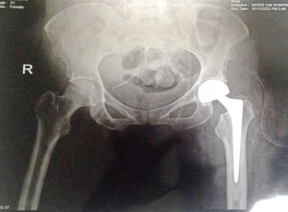

31 year old female presented to us with complaints of limp while walking from past few months. No history of fever, loss of appetite, weight loss or any other constitutional symptoms. Patient is a post operated case of Medulloblastoma brain and occipital craniotomy with VP shunting was done in May 2018 in London for the same along with adjuvant chemo-radiation. Patient received craniospinal radiotherapy (35Gy/21fractions) + (20Gy/12 fractions) for approx. 6 weeks in Aug-Sep 2018. Patient received 6 cycles of Cisplatin, Vincristine and Lomustine, during Sep 2018-Dec 2018. Patient was on regular follow up and regular MRI Brain was done during follow up and patient was asymptomatic during the time period of last 4 years, until last month when she developed sudden onset right lower limb limp while walking. Patient was evaluated for above mentioned complaints and relevant scans were done. On X ray (Fig. 1),   MRI (Fig. 2) and PET scan (Fig. 3) multiple lytic lesion were seen involving D7 vertebra, right ischium and left proximal femur. Left proximal femur lesion was measuring 5.5 x 3.8 x 3.2 cm with a cortical breach. CT guided biopsy from D7 vertebra was done which showed typical emperipolesis (Fig. 4) S/O Rosai Dorfman Disease. IHC was done and was positive for S100 and CD68 suggestive and negative for CD1a suggestive of Rosai Dorfman Disease. High risk of pathological fracture of left proximal femur (Mirel’s Score – 11) was explained to the patient and cemented bipolar hemiarthroplasty was done for left hip. Post op patient was mobilized on Day 1 and dressing was changed at Day 5 and patient was discharged at Day 6. Final histopathology impression was s/o Extranodal Rosai Dorfman disease.

Fig. 1(a) Pre op X ray                                   (b) Post op X ray